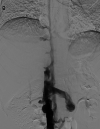

A young adult male was referred for a second opinion of deranged liver biochemistry. He initially presented two years prior with abdominal pain, lethargy and fevers due to a segment two pyogenic liver abscess. He received empirical antibiotic therapy to resolution. Computed tomography for abscess follow-up revealed an intrahepatic inferior vena cava thrombus. He was anti-coagulated with warfarin. He was lupus anticoagulant positive and had a highly positive beta-2 glycoprotein antibody on serial measurement and was diagnosed with anti-phospholipid syndrome. On current review, the patient had no clinical stigmata of chronic liver disease. There were dilated veins on the supraumbilical abdominal and chest walls. There was mild hepatomegaly but no splenomegaly. Laboratory investigations revealed mildly cholestatic liver function tests with hyperbilirubinaemia (40μmol/L) but no liver synthetic dysfunction. Serological screening did not reveal any cause of chronic liver disease. The patient underwent multiphase abdominal CT and formal hepatic venography. What is the diagnosis and describe the hepatic venous outflow?